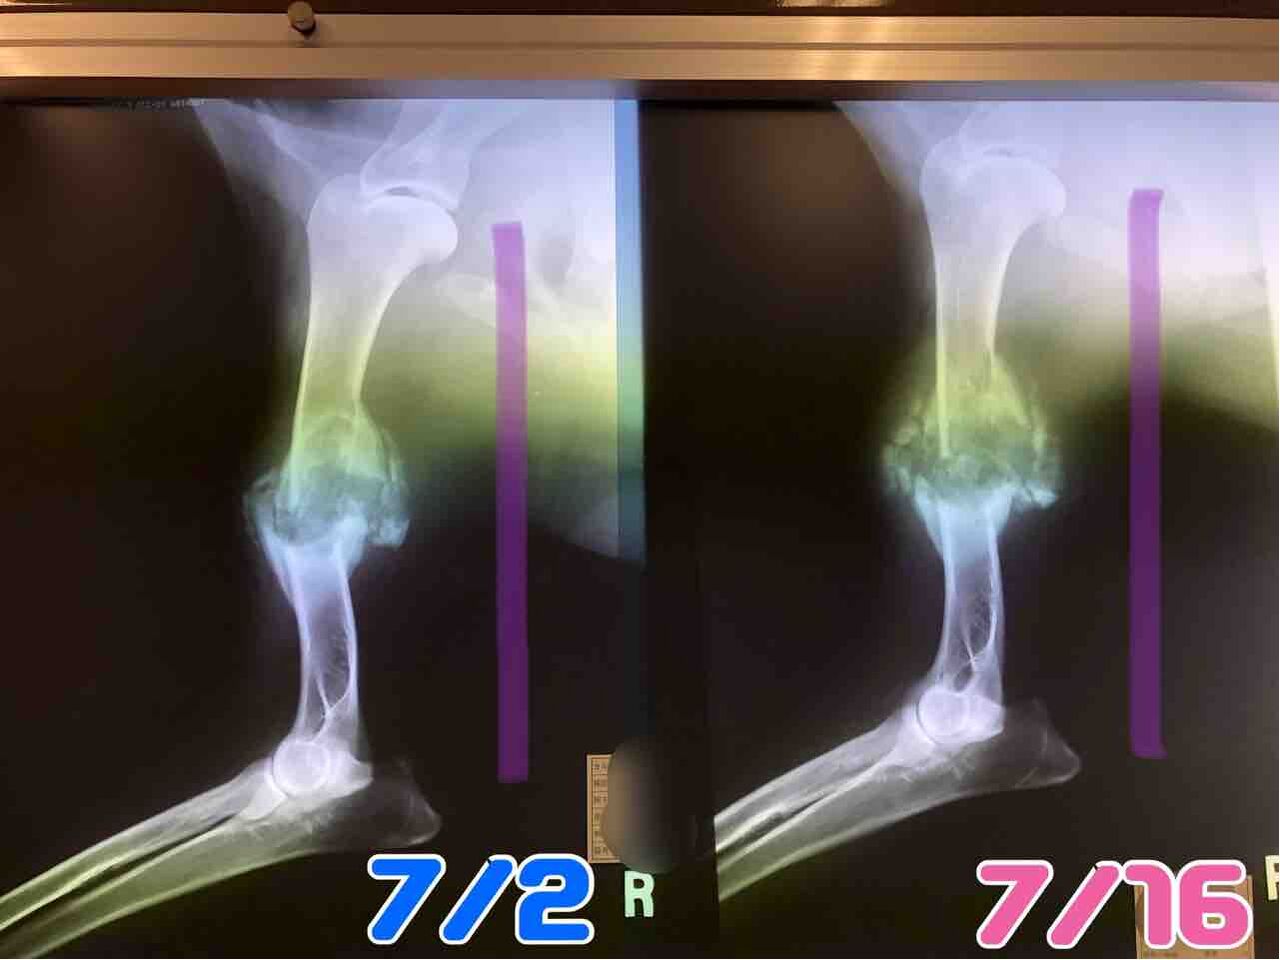

やっぱり、左後ろ脚と右前脚の検査結果は「腫瘍」でした。

細胞検査なので、何腫瘍かははっきりとはわからないけど、普通の骨肉腫とは違い特殊な腫瘍かと。

(腫瘍で骨が溶けてます)

右前脚も後ろ左脚も同じように骨が溶けてきているんだけど、後ろは腫瘍が大きくなるのがめちゃくちゃ早い。体調は良いです。

右前脚も後ろ左脚も同じように骨が溶けてきているんだけど、後ろは腫瘍が大きくなるのがめちゃくちゃ早い。